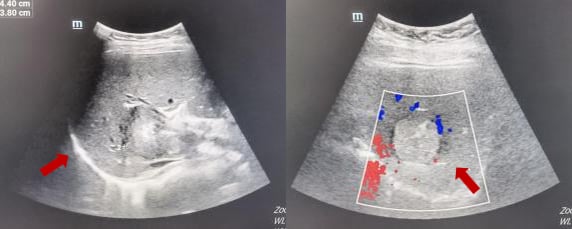

不幸的是,在无病生存24个月后,2015年7月,患者出现第一次复发,胸部CT显示右肺及左肺上叶、胸膜下多发软组织结节,考虑转移。头颅CT、骨扫描、腹部CT未见明显异常。BRCA基因检测未发现明确致病突变。

- 一线维持治疗:戈舍瑞林(卵巢功能抑制剂)+来曲唑(芳香化酶抑制剂)进行内分泌治疗,疗效评价为部分缓解(PR)。